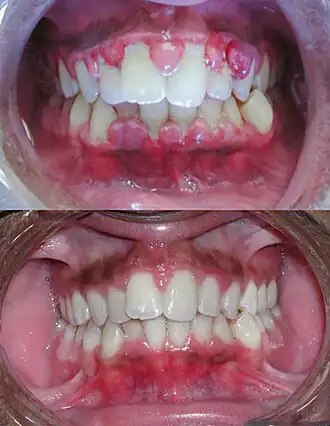

| Gengivite severa antes do tratamento na imagem de cima e depois do tratamento por debridamento mecânico na imagem de baixo. | |

Gengivite é o processo inflamatório que ocorre na gengiva que geralmente decorre do acúmulo de placa bacteriana, também chamada de biofilme dental, devido a falta de higiene bucal adequada do indivíduo e pode estar relacionada ao estado imune do indivíduo em alguns casos. A irritação tecidual provocada pela placa bacteriana tem como principais características a alteração da coloração da gengiva que se torna avermelhada, também apresentando textura e forma alteradas. Entretanto o sangramento tende a ser o sinal mais evidente desta condição inflamatória. Pode ocorrer sangramento à sondagem realizada pelo profissional durante a consulta de diagnóstico, todavia não é incomum que o indivíduo perceba a presença do sangramento ao realizar a escovação dentária e/ou ao passar o fio dental na região interdentária.[1]

Devido ao fato da gengivite não existir sem um grupo bacteriano envolvido, o seu tratamento se resume ao aumento da higienização bucal do hospedeiro, visando controlar a formação de placa-bacteriana nos dentes. Em casos onde o indivíduo sofre de alguma imunodeficiência, é de suma importância que seja feito o acompanhamento com um dentista, para que assim uma limpeza profunda possa ser feita.